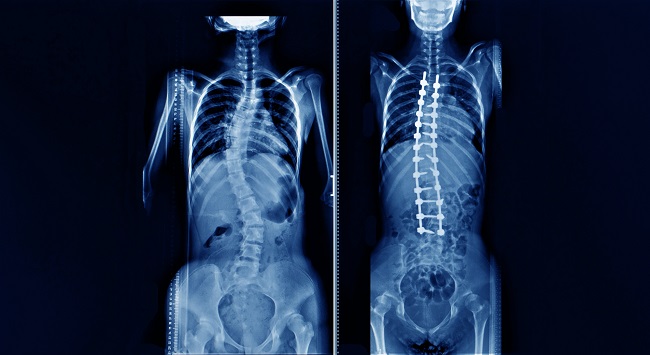

Skoliosis merupakan deformitas torsional vertebra secara tiga dimensi, yaitu kelengkungan ke lateral pada bidang frontal, rotasi aksial pada bidang horizontal, serta perubahan kurvatur di bidang sagital.

Abnormalitas fungsi paru pada skoliosis umumnya berupa gangguan paru restriktif yang mulai terdeteksi saat sudut Cobb lebih dari 50–60°, sedangkan sudut Cobb >90° merupakan predisposisi gagal napas. Ragam dampak skoliosis pada sistem respirasi dapat terjadi pada paru, otot–otot pernapasan, jaringan ikat hingga saluran napas.[4,5]

Gangguan paru tipe restriktif pada skoliosis dipengaruhi besar derajat sudut Cobb, lokasi kelengkungan, rotasi vertebra, serta hilangnya kurva kifosis pada segmen vertebra torakal. Semakin tinggi lokasi kelengkungan dari vertebra torakal, semakin berat kompresi sisi paru di sisi konveks skoliosis.

Rotasi vertebra turut menyebabkan pergeseran costae ke lateral, sehingga terjadi kompresi dan distorsi paru ke arah lateral. Perubahan volume paru ini menyebabkan penurunan fungsi paru, yaitu kapasitas paru total (total lung capacity/TLC) dan kapasitas vital. Didapatkan adanya korelasi antara kapasitas vital dengan sudut Cobb dan panjang kurva.[4,6]